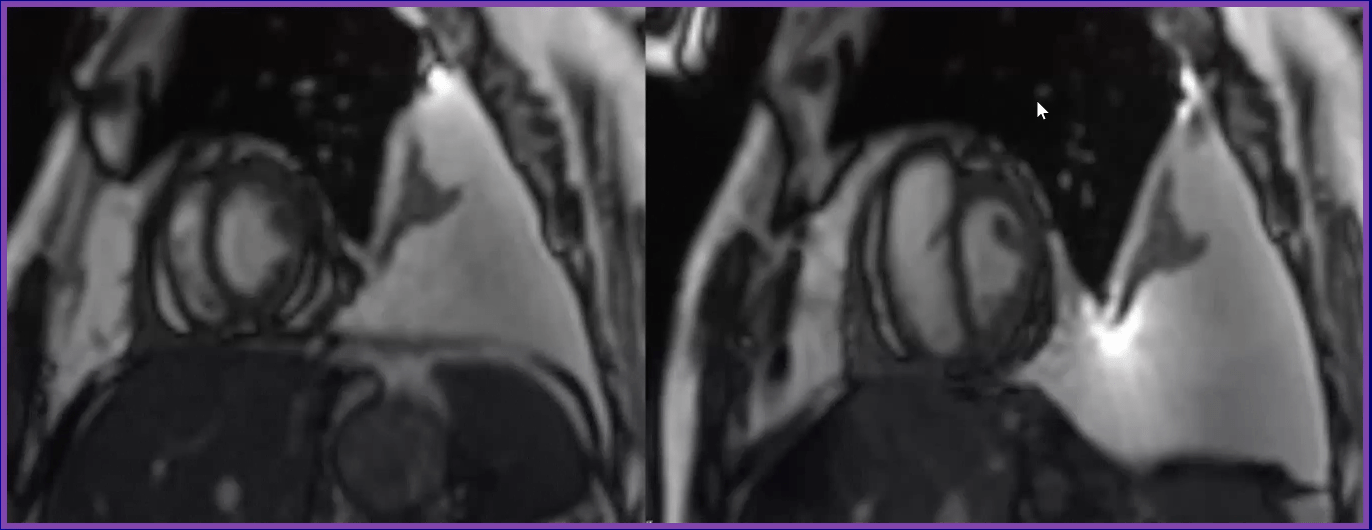

The diagonsis portrayed by the image is...

What is constriction or constrictive pericarditis?

-Note the position of diagphragm

-The left is expiration, and the right is inspiration

-With inspiration there is increased filling of the RV as noted by the increase in size. Because there is a realtively fixed pericardial space, the increaded RV filling reduced LV filling and results in flattening of the interventricular septum.